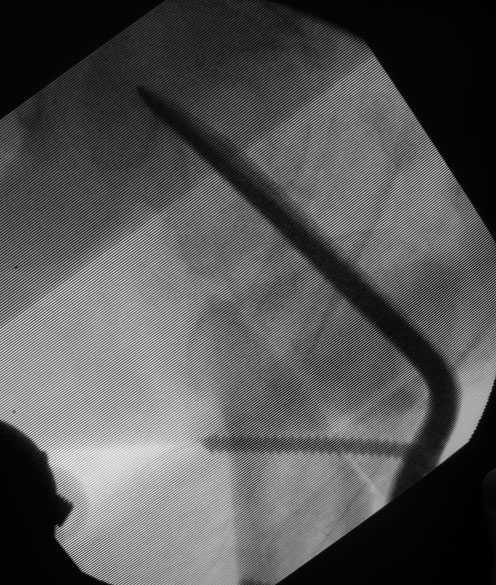

1. судя по снимкам, не складывается впечатление, что речь идет о ложном суставе шейки бедра – скорее, оскольчатом трохантерном переломе

2. фиксация проксимального отдела бедра неоптимальна ( blade plate проходит через верхнюю , наиболее порозную часть шейки бедра). Вряд ли 6 (!) шурупов в дистальный отдел бедра добавляют прочности данному импланту.

по-моему, остеотомия выполнена немного выше оптимального уровня.

Да, 2-3 винтов было бы достаточно. Реально работают самый нижний и самый верхний винты.

blade в нашем случае явно в верхней, наиболее порозной части шейки и головки ( в отличие от описанного в статье), так что риск коллапса и "прорезания" лезвия в сустав при ранней нагрузке крайне велик

"blade в нашем случае явно в верхней, наиболее порозной части шейки и головки". В "нашем" случае blade установлено в крайний нижний сегмент головки, т.е. в самый прочный и не порозный. Это можно уведеть сравнив первичные снимки представленные 16.11.08 и косвенно по просветлению в головке (место бывшего расположения динамического винта) располающемуся ВЫШЕ клинка.

ОК, в центре ( ну уж никак не в наиболее нижнем сегменте :) головки и в верхней части шейки ( честно говоря, у меня складывается ощущение, лезвие входит в шейку либо сверху, а не через перелом, либо по верхнему кортикалу, но настаивать не буду - разрешение снимков недостаточно, чтоб говорить об этом с уверенностью)